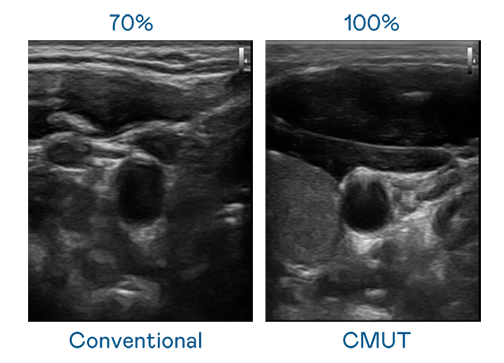

CMUT 技术是一种用电容式微机电元件来产生超音波讯号的技术。与传统 PZT 压电式技术相比,CMUT 频宽增加 30%,更宽频的超音波讯号让影像解析度大幅提升,是实现高影像品质医疗超音波扫描、促进精准医疗发展的关键技术。

大频宽带来超清晰影像

超音波影像的解析度高低,首先取决于探头能发出的讯号频宽。维多利亚老品牌vic119 CMUT 可提供高清晰的超音波讯号,提供高频宽、高灵敏度、影像纹理细节更高的超音波影像,协助医护人员缩短影像判读时间及利用精准的医疗影像进行诊断。